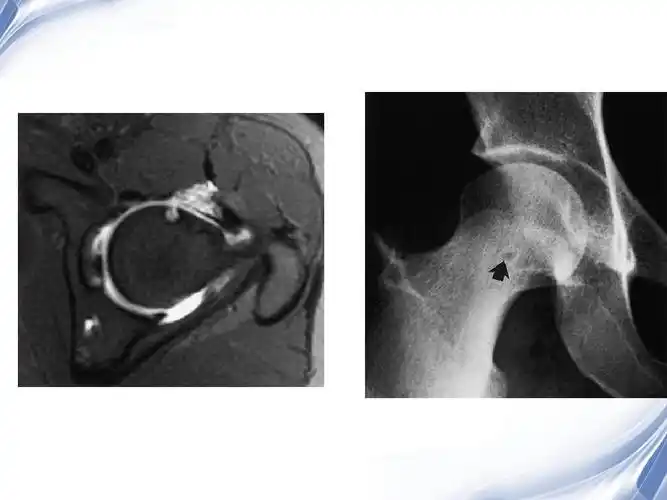

医学影像-股骨颈疝窝ppt

股骨颈疝窝(滑膜疝凹)于1982年由pitt等首先报道.

股骨颈疝窝

股骨颈疝窝的ct及mri诊断_手机搜狐网